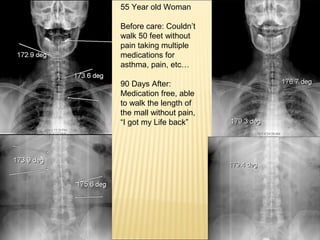

37. 55 Year old Woman Before care: Couldn’t walk 50 feet without pain taking multiple medications for asthma, pain, etc… 90 Days After: Medication free, able to walk the length of the mall without pain, “I got my Life back”

42. 14% reduction in Scoliosis in 90 days in a Patient 68 Y.O. High BP, High Cholesterol, High Blood Sugar Before After